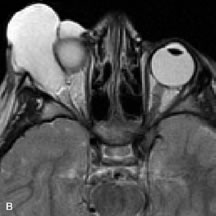

Cavernous hemangiomas appear as well-circumscribed, smooth, usually intraconal masses that are isointense to muscle on T1-weighted images and hyperintense on T2-weighted images (Fig. 12). Patchy early enhancement is typically followed by diffuse, more homogeneous enhancement.39 The internal architecture of the mass, including septation and internal vasculature, may often be appreciated with high-quality orbital imaging.40

Fig. 12. A. T1- and (B) T2-weighted MR scans demonstrate a well-circumscribed intraconal mass causing severe optic nerve displacement. These lesions are usually intermediate in signal intensity on T1-weighted scans and very hyperintense on T2-weighted Images. C and D. Postcontrast fat-suppressed T1-weighted scans demonstrate characteristic patchy intense enhancement that becomes more complete from the initial postcontrast scan (C) to a more delayed scan (D).